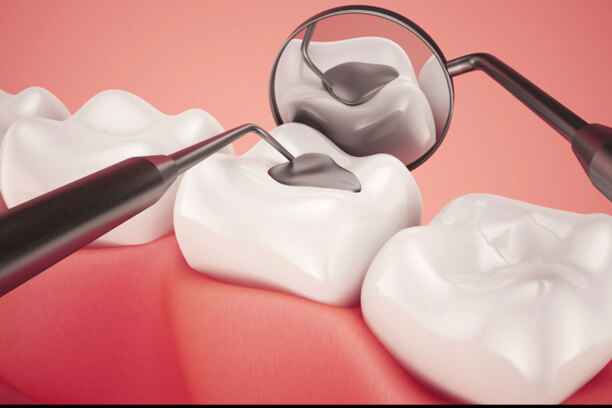

ما هي حشوة الاسنان الامامية؟

حشوة الأسنان الأمامية ليست مجرد مادة تُوضع داخل السن، بل هي عملية ترميم دقيقة تهدف إلى استعادة الشكل والوظيفة في آنٍ واحد.

- تُستخدم لعلاج التلف أو التسوس أو الكسور التي تصيب الأسنان الأمامية، مع الحفاظ على مظهر طبيعي يصعب تمييزه عن الأسنان الأصلية

- تعتمد على مواد حديثة مثل الكمبوزيت التي تُصمم بدرجات لونية متعددة لتتناسب تمامًا مع لون الأسنان

- تساعد في تقوية بنية السن ومنع تفاقم المشكلة، مما يطيل عمره ويحافظ على سلامته

هذا الإجراء البسيط ظاهريًا قد يكون الفارق الحقيقي بين ابتسامة عادية وأخرى آسرة.